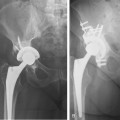

The site of the fracture, stability of the prosthesis, and quality of the bone stock determine fracture severity (Fig. 57-3). In type A, the greater or lower trochanter is affected. Type B fractures are those at or just distal to the stem tip. Type B has three subtypes: B1, in which the prosthesis is stable; B2, in which there is a loose prosthesis but adequate bone stock; and B3, in which the prosthesis is loose and there is marked proximal bone loss or damage to a degree that a standard revision component will not be supported. Type C fractures are well distal to the stem tip.